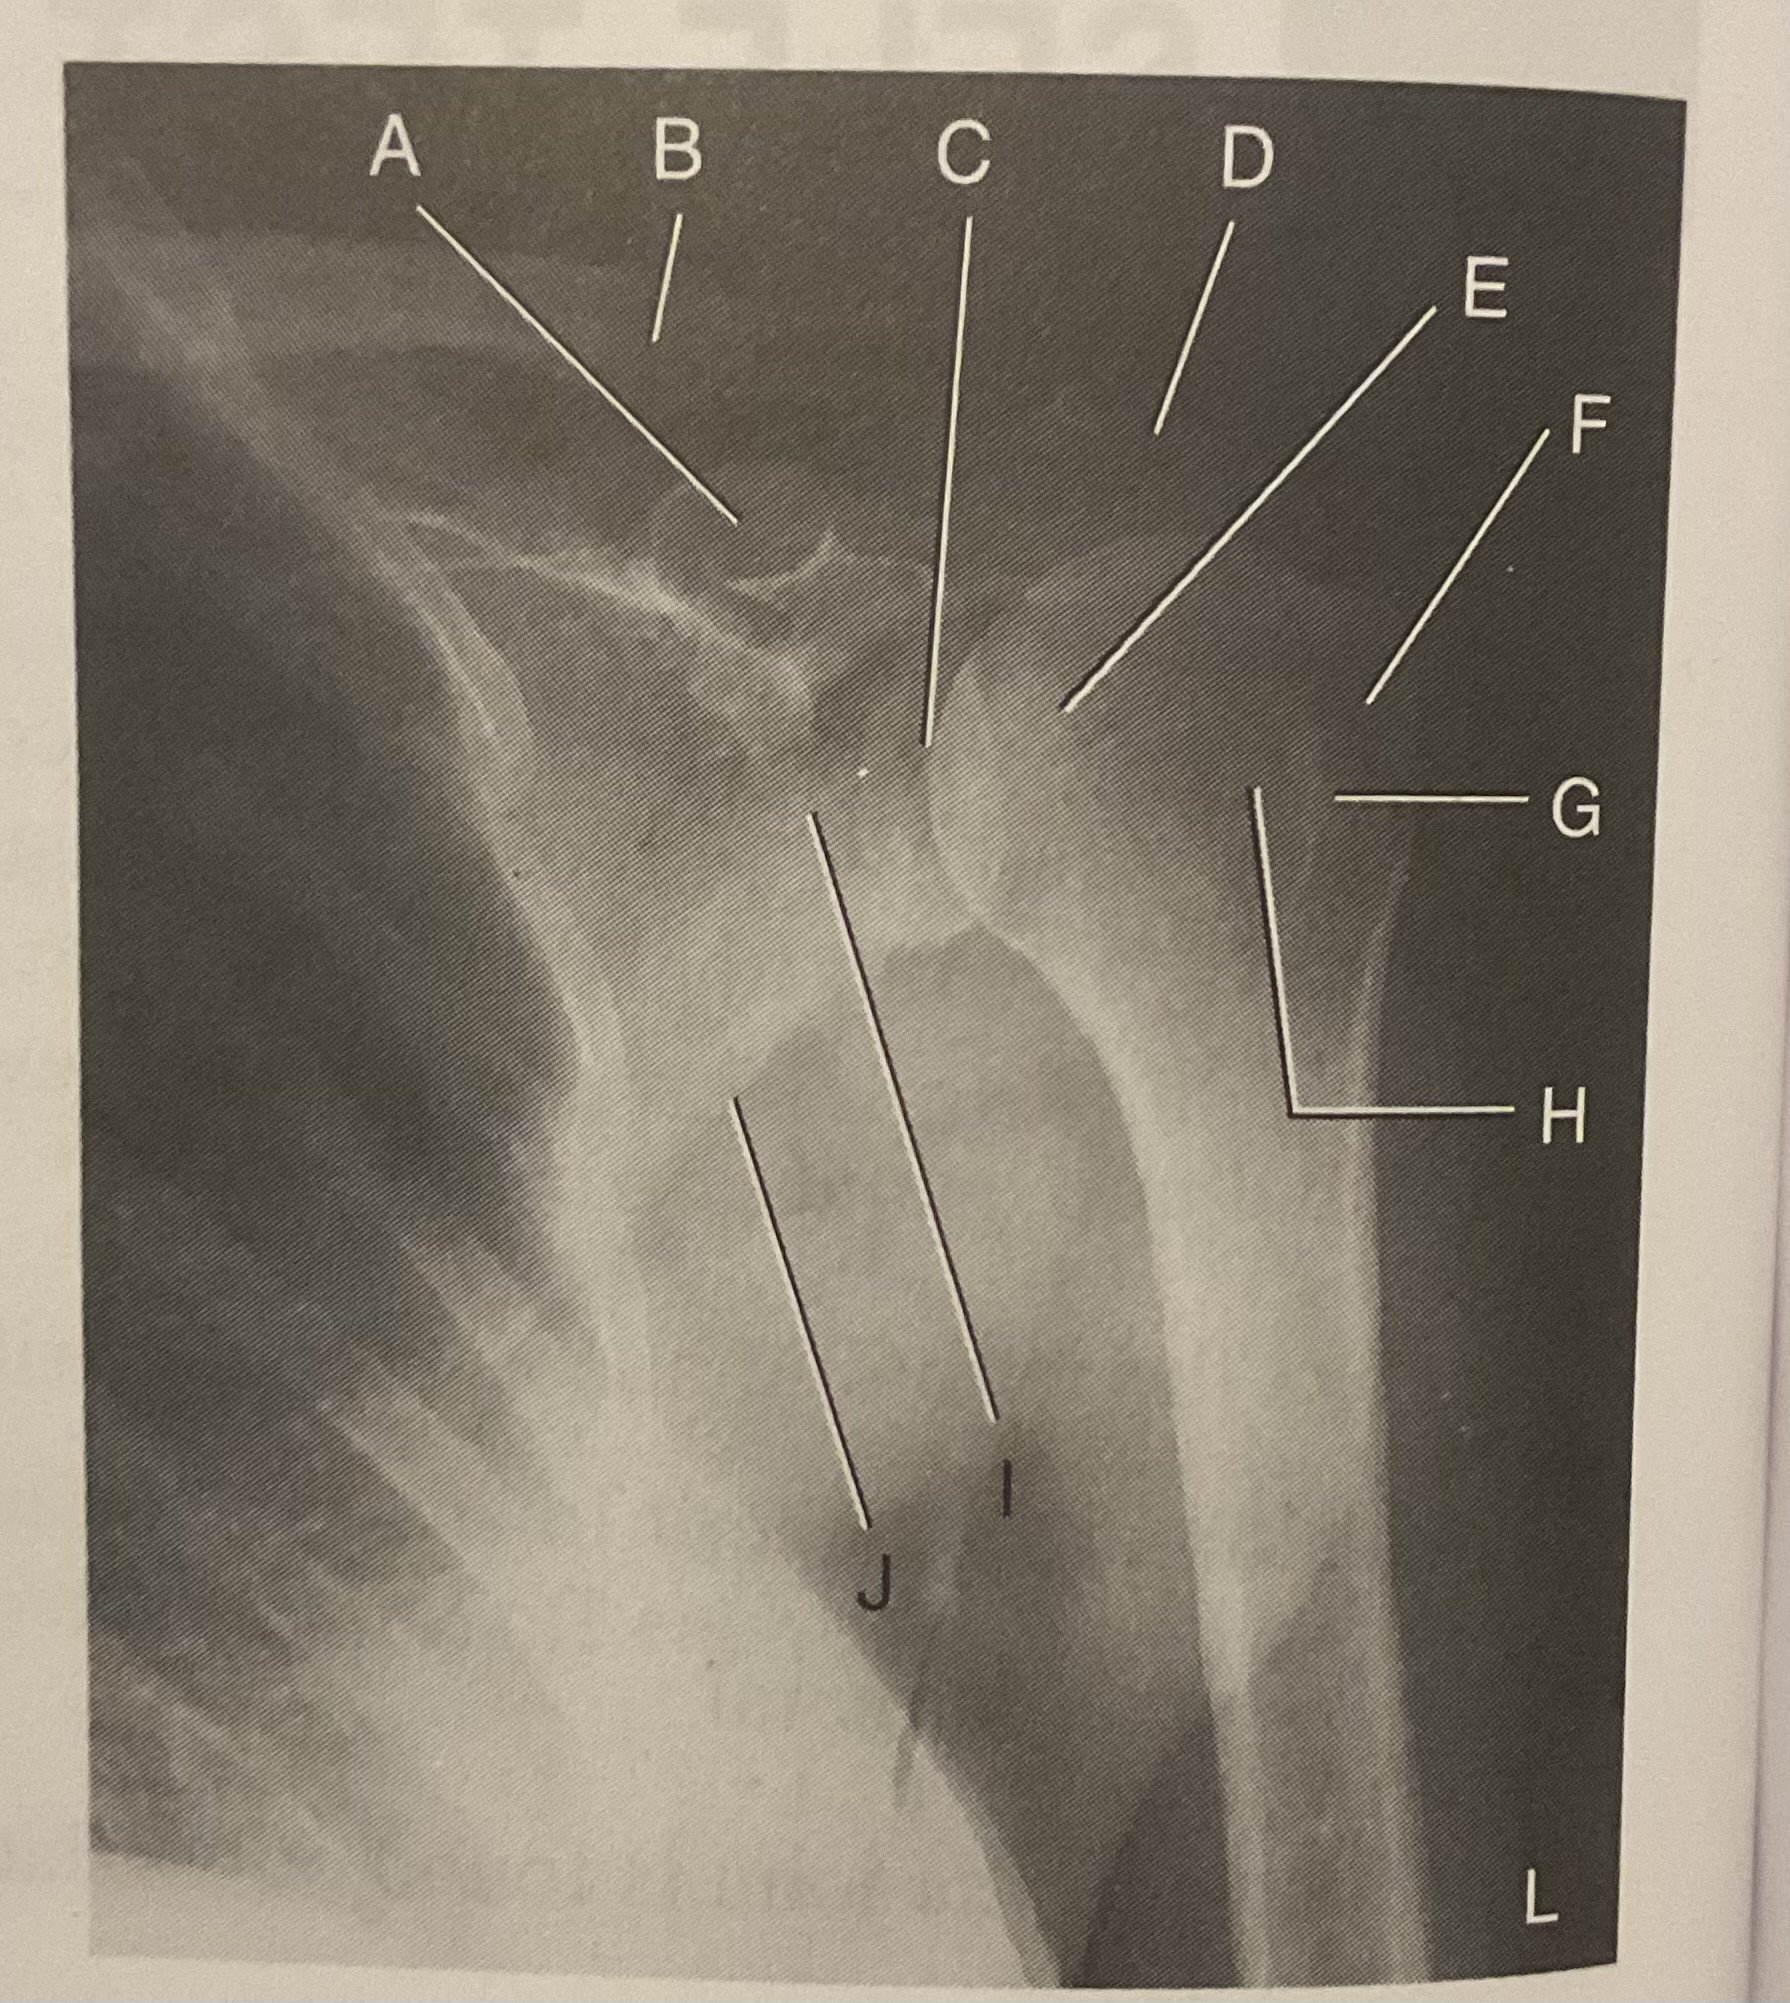

A?

Coracoid process

B?

Clavicle

C?

Scapulohumeral joint

D?

Acromion of scapula

E?

Head of humerus

F?

Greater tubercle

G?

Intertubercular sulcus

H?

Lesser tubercle

I?

Neck of scapula

J?

Lateral (axillary) border of scapula

What AP projection does this image represent?

External